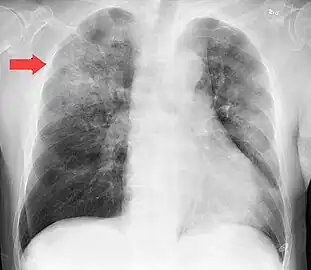

Chest X-ray of a pneumonia caused by influenza and Haemophilus influenzae, with patchy consolidations, mainly in the right upper lobe (arrow)